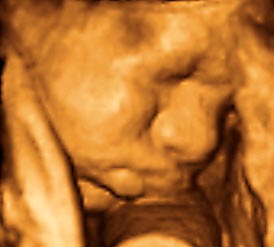

香港结构超声波照片

结构性超声波, 四维 香港, 四维结构性超声波 结构性超声波, 四维 结构性超声波, 四维 香港, 四维结构性超声波 结构性超声波, 四维 香港, 四维结构性超声波 结构性超声波, 四维 结构性超声波, 四维 结构性超声波, 四维 香港, 四维结构性超声波 结构性超声波, 四维 香港, 四维结构性超声波 结构性超声波, 四维 结构性超声波, 四维